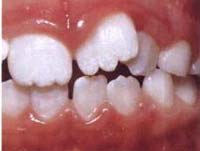

+Răng dư bẩm sinh (Mesiodent):

• Do bất thường từ mầm răng. Răng dư rất thường gặp nhất là ở vùng răng cửa giữa nên mới gọi là mesio, răng dư thường nhỏ và hơi dị dạng nằm chen lẫn giữa các răng. Răng dư thường gặp là răng số 1bis, răng số 4bis, rất hiếm có răng cối lớn (răng hàm) bị dư. Răng dư thường mọc lệch hoặc chen chúc nhau trên hàm, nếu muốn chỉnh răng phải nhổ bớt các răng dư.